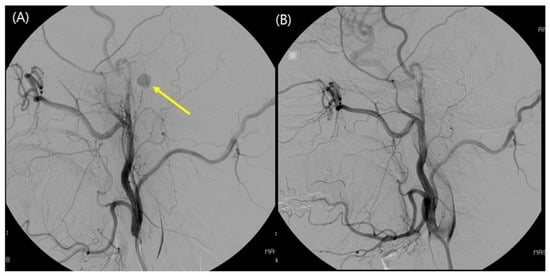

2.5. Surgical Management

3.2. Intraoperative Findings

3.5. Complications